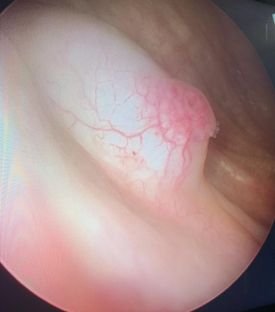

Prostate Surgery

Prostate problems are not uncommon, and they affect a significant number of men worldwide. As men age, the risk of developing prostate issues, including prostate cancer, increases. This makes it crucial to understand the treatment options available.

Prostate problems are not uncommon, and they affect a significant number of men worldwide.